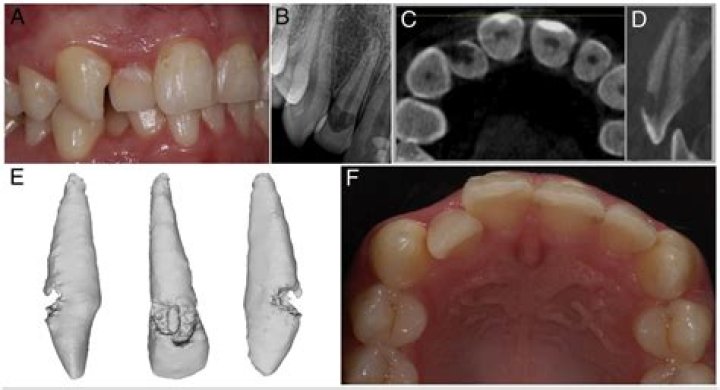

Cervical external resorption also called as invasive cervical resorption is a clinical term used to describe a relatively uncommon, insidious and often aggressive form of external tooth resorption, which may occur in any tooth of permanent dentition.

External resorption is initiated in the periodontium and affects the external or lateral surfaces of a tooth. It is a common sequelae following traumatic injuries, orthodontic tooth movement, or chronic infections of the periodontal structures.